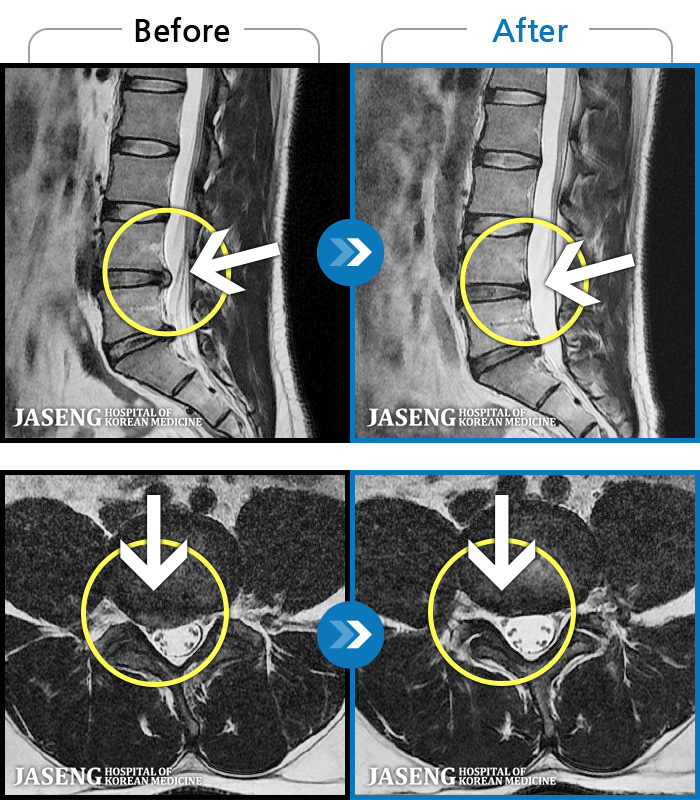

- MRI ġ

MRI ġ

1,240 MRI ũ ʸ Ȯϼ.